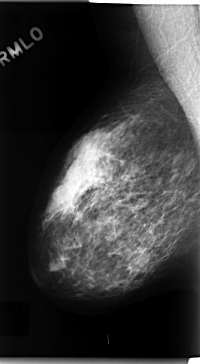

C_0222_1.RIGHT_MLO

RIGHT_MLO LINES 4728 PIXELS_PER_LINE 2600 BITS_PER_PIXEL 12 RESOLUTION 50 NON_OVERLAY